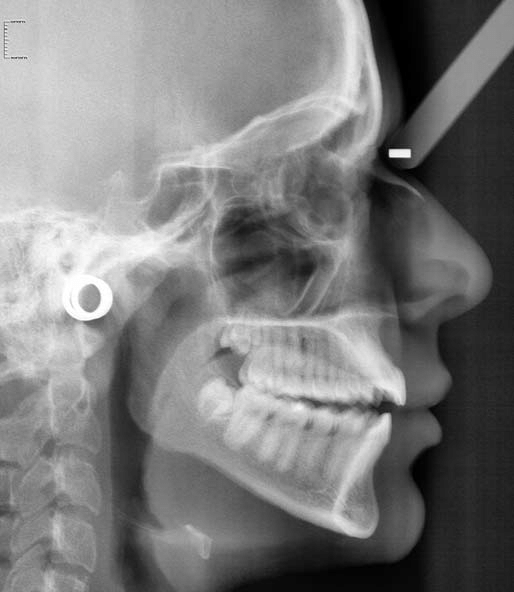

2)Cephalogram

यात जबड्याचा व डोक्याचा एका बाजूने एक्स-रे काढला जातो.

विशेषतः दात पुढे असणे किंवा दातांना तार लावण्याच्या ट्रीटमेंटच्या आधी व नंतर हा एक्स रे काढावा लागतो